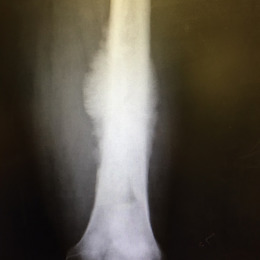

Radiographic imaging is used to help form a diagnosis. These include X-Ray, MRI, CT and Bone Scans.

An example of a Conventional Osteosarcoma X-Ray is shown.